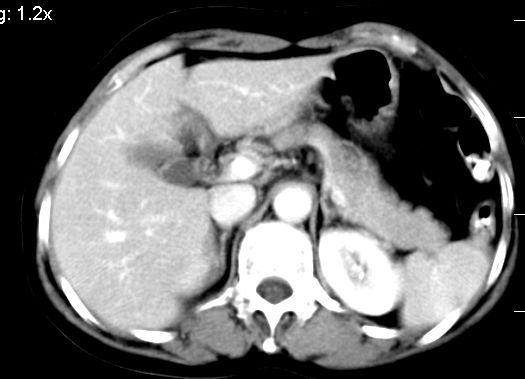

肝大小形态未见异常,肝内外胆管无扩张,肝s8段见一动脉期明显血管样强化结节,门脉期呈高密度,延迟期呈等密度,胆囊不大,增强扫描见胆囊及胆囊颈管壁增厚,有强化。

双肾灌注良好,代谢增快,动脉期肾盂见造影剂,左肾下极背侧见一略低密度病灶,延迟期见似不强化囊肿,双侧肾上腺未见异常。

胰腺及脾未见异常。肾门水平腹膜后见小淋巴结。腹腔未见积液征象。